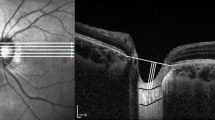

Representative cases showing the differences in LCCI in eyes with and without focal LC defects are presented in Fig. 2. LC curvature was considerably smaller in the eye with (Fig. 2a) than without (Fig. 2b) focal LC defect.

Representative eyes with (a) and without a (b) a focal LC defect. (a-1, b-1) Disc photographs of the left eye of a 75-year-old man (a), and a 50-year-old woman (b). (a-2, b-2) B-scan images obtained at the locations indicated by the green arrows in a-1and b-1, respectively. The focal LC defect is indicated by the green arrow head (b-2). Note that LCCI was smaller in the eye with (a-2, red dots) than without (b-2, red dots) a focal LC defect. However, retinal nerve fiber layer thickness (a-3, b-3) and visual field damage (a-4, b-4) did not differ between these two eyes. (a-5, b-5) Green dashed lines indicate the optic disc margin, and the red arrow indicates MvD (a-5). Note that the parapapillary MvD was located at the same sector as the focal LC defect.